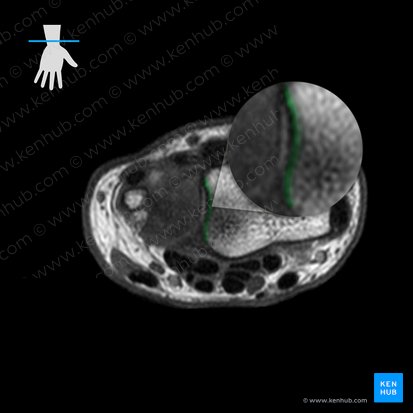

The distal radioulnar joint is the articulation between the crescent-shaped convex distal head of ulna and the concave ulnar notch of radius. Both surfaces are lined by the hyaline cartilage.

The joint contains a triangular fibrocartilaginous articular disc. The apex of the disc is attached to the lateral surface of the styloid process of ulna, while the base is anchored to the inferior margin of the ulnar notch of radius.

Besides taking part in the distal radioulnar joint, the disc participates in the radiocarpal joint with its inferior surface. The disc is thinner centrally than peripherally, meaning that a potential perforation of its central part would open the communication between the distal radioulnar and radiocarpal joints.

Triangular fibrocartilage complex (TFCC)

The triangular fibrocartilage complex (TFCC) is a biconcave ligamentous complex that stabilizes and cushions the joints of the wrist region; distal radioulnar, ulnocarpal and radiocarpal joints. It consists of the articular disc of the distal radioulnar joint, ulnar collateral ligament, dorsal and palmar radioulnar ligaments, the base of the extensor carpi ulnaris sheath, and the ulnolunate and ulnotriquetral ligaments.

The core of the TFCC is the articular disc of the distal radioulnar joint. The dorsal and palmar parts of the TFCC are thickened and known as the dorsal and palmar radioulnar ligaments, respectively. Each of these ligaments consists of the superficial and deep components which differ by their ulnar attachments. The superficial components insert onto the styloid process of ulna, while the deep ones insert slightly more laterally. The ulnar collateral, ulnolunate and ulnotriquetral ligaments join the TFCC on its ulnar attachment. The dorsal margin of the TFCC is fused with the floor of the base of the extensor carpi ulnaris sheath.